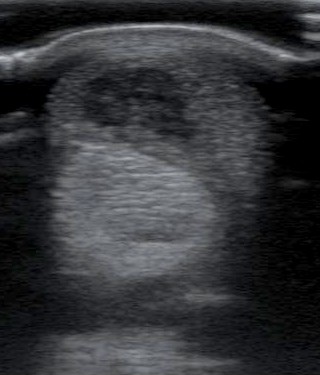

Egy kifejezetten nagy defekt az ín közepében.